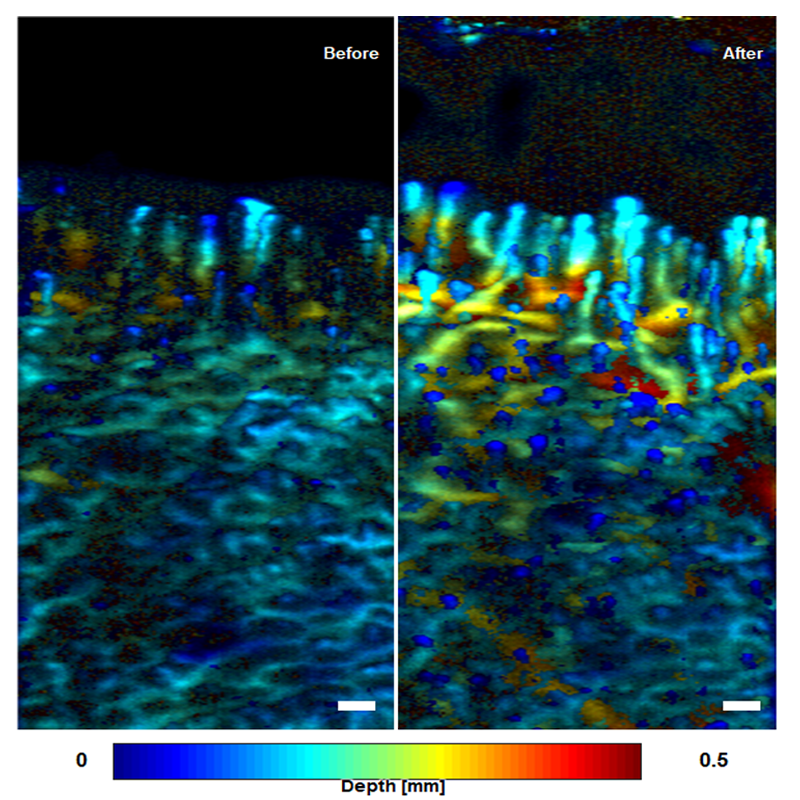

Dermatological diseases

J. W. Baik et al., IEEE Transactions on Medical Imaging Vol 39, 975 (2020)